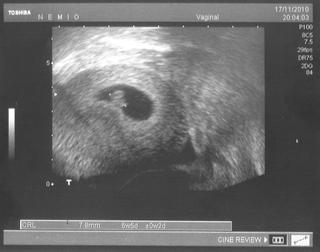

@embabuli aha toto je nas cervicek...teraz je uz ovela vacsi...toto je z 10tt+6

A ja nemam take hrozne nevolnosti. Teda jeden den ano, dalsi nie a tak sa to strieda. Hlavne ked mam prazdny zaludok. Ale az tak ma tie nevolnosti netrapia. Akurat ma zacala trapit opat mykoza. Dnes, alebo zajtra musim ist na gyndu. Hlavne ze v pondelok ked som tam bolo, som mala vraj vsetko v poriadku no a od vcera svrbenie a palanie. Uz vidim ze ma to bude trapit cele tehu.

@chomica fuu tak to uz je ale velikan! nadherne 🙂

@embabuli no a keby si vedela aky bol nas certik teraz v pondelok uz velky...na celu dutinku...sa hybal a kyval ruckami 🙂